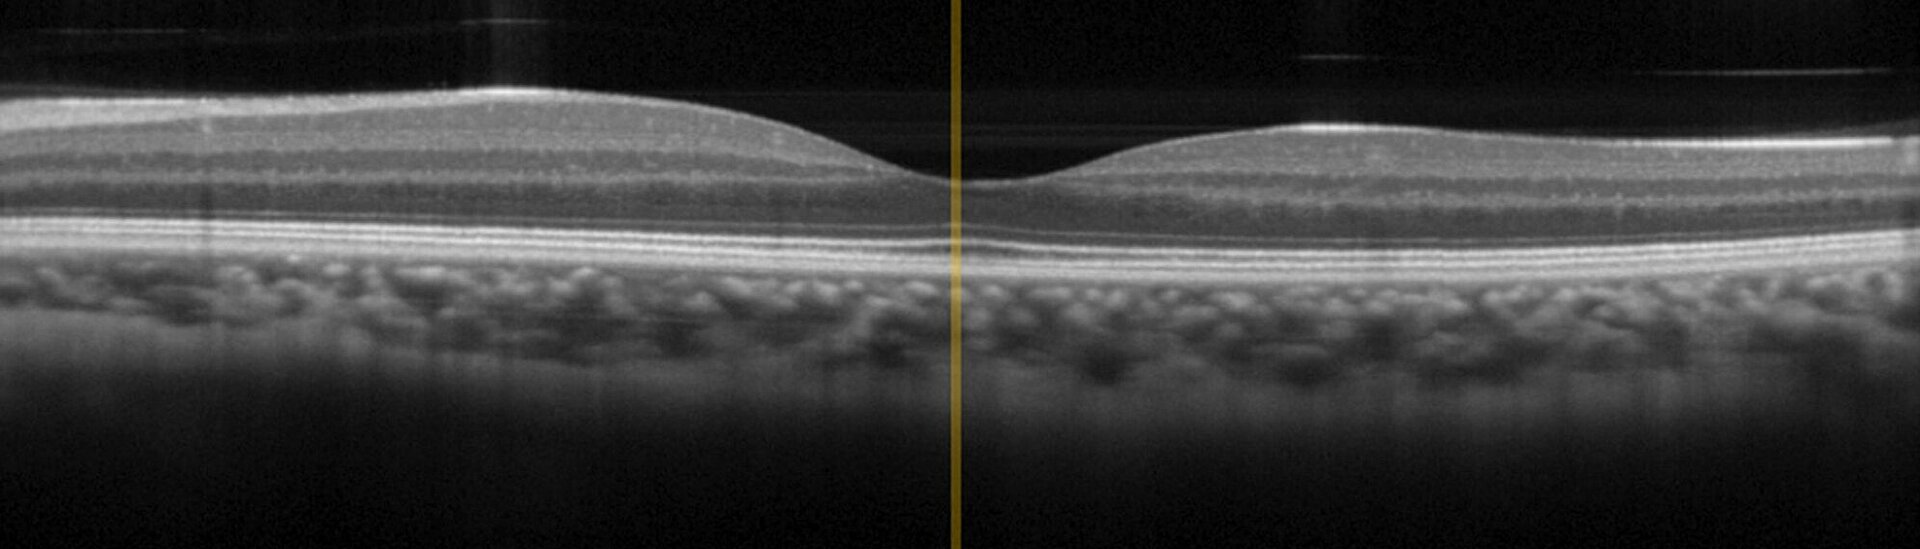

OCTは、組織への最適な透過性を実現するための、0.8μmから1.4μmの波長域の広帯域赤外光による干渉イメージング技術です。OCTはすでに眼科学において 「ゴールドスタンダード」 に達していますが、近年では皮膚がんの診断など、皮膚病学への応用も広がっています。従来の侵襲型の診断法と比較し、OCTはより迅速に結果をもたらし、患者への副作用やストレスを軽減します。

OCT技術はマイケルソン干渉装置においてコヒーレンス長が短い広帯域IR光 (組織への浸透が最適な800~1400 nmの波長領域) を使用しています。信号は、生体組織内の屈折率境界での反射に基づく、プローブ- および参照-ビームからの干渉の結果です。